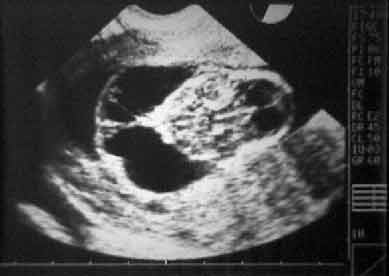

Caryotype fœtal

Euploidie

Aneuploidie

Monosomie

Trisomie 21 Trisomie 18 |

6

5 2 |

27

25 8 |